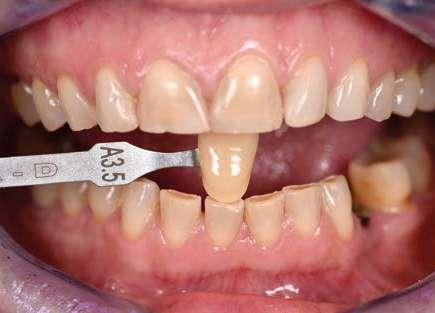

A continuación, presentamos el caso clínico de una paciente con unos dientes mal posicionados y con una coloración acentuada sobre todo a nivel de los centrales que además presentaban extensas restauraciones antiguas de composite en interproximal cerrando diastemas que originalmente presentaba la paciente. Estos dientes necesitarán tener una preparación un poco más subgingival y también removido previamente todo el composite antiguo con el objetivo de camuflar este cambio de color y evitar zonas visiblemente no estéticas.

Como podemos observar la paciente tenía un sustrato muy desfavorable, con un color aproximado de A3,5 Vita.